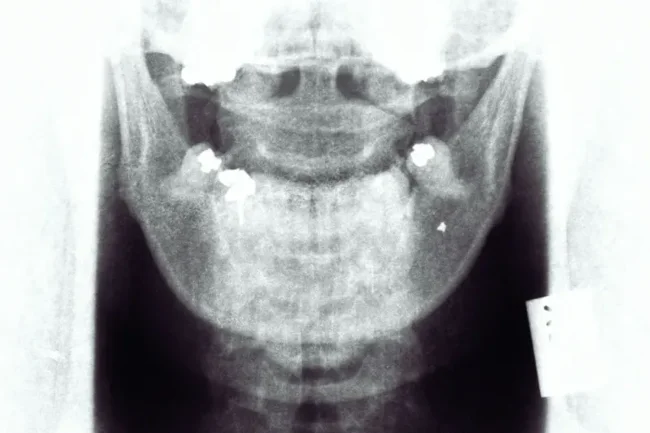

The AI suggested that he had a displaced disk, and shared with the user instructions on how to fix it.